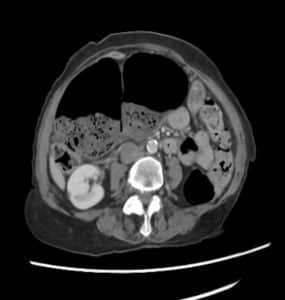

Blood investigations revealed a C-reactive protein (CRP) of 56 mg/L, with no leucocytosis or abnormalities in arterial blood gases. A subsequent abdominal computed tomography (CT) scan showed a loop of bowel with characteristic “coffee bean” morphology extending from the right iliac fossa towards the left upper quadrant, containing formed stool and gas, consistent with a diagnosis of caecal volvulus (Figure 1).

Figure 1. CT images of the abdomen showing the “coffee bean” morphology indicative of caecal volvulus

Rectal prolapse and abdominal pain occurring together may be indicative of various underlying conditions. Chronic constipation can weaken the supportive tissues of the rectum, leading to prolapse, while the straining associated with constipation can also cause abdominal discomfort. [10] Pelvic floor dysfunction, characterized by weakness or coordination issues in the pelvic muscles, can contribute to both prolapse and abdominal discomfort.[11] Complications of rectal prolapse, such as incarceration or strangulation, can lead to significant abdominal pain requiring urgent medical attention.[12] Inflammatory bowel diseases like Crohn’s disease or ulcerative colitis may cause inflammation and damage in the rectum and colon, resulting in both prolapse and abdominal pain.[13] Additionally, pelvic inflammatory conditions, neurological disorders affecting bowel function, tumours, or masses in the pelvic or abdominal region, and traumatic injuries to the pelvic area can all contribute to the simultaneous occurrence of rectal prolapse and abdominal pain.[9,15,16,17] However, the characteristic CT findings, particularly the “coffee bean” sign, led to the definitive diagnosis of caecal volvulus. While these conditions were initially considered, the CT findings ultimately ruled them out in favour of the diagnosis of caecal volvulus.[6,7]

Prompt diagnosis and intervention are paramount in managing such cases to prevent complications like bowel ischemia and necrosis. In this instance, timely surgical consultation and imaging studies, particularly a CT scan, facilitated accurate diagnosis and appropriate management. The CT findings, including the characteristic “coffee bean” sign indicative of caecal volvulus, effectively guided the surgical team in planning the intervention. While the CT scan is a valuable diagnostic tool, it is essential to acknowledge that there may be limitations or potential pitfalls in its interpretation, particularly in rare presentations such as this one.[6,7]